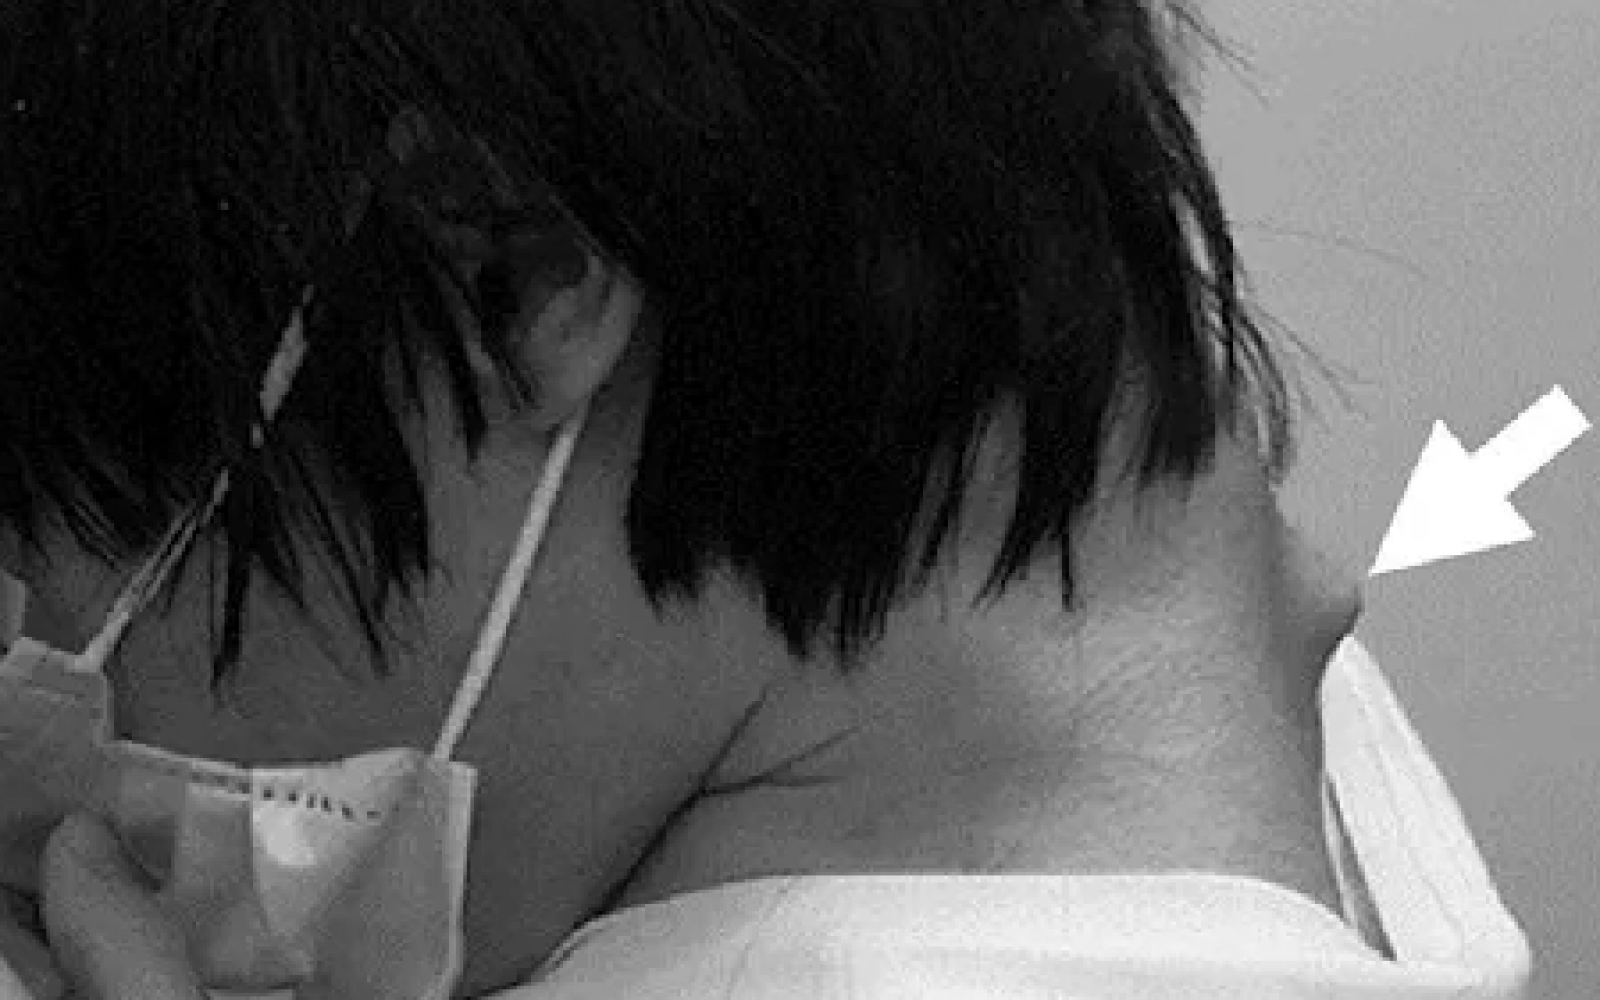

25-letni ljubitelj igric je več let pretiraval z buljenjem v telefon, zaradi česar je utrpel hude zdravstvene težave. Japončeve vratne mišice so zaradi vsakodnevne nenaravne lege, ki je trajala tudi po več ur, oslabele, kar je pripeljalo do poškodbe hrbtenice in bule na vratu. Zdravniki so pri mladem moškem, ki ni mogel več dvigniti glave, diagnosticirali sindrom spuščene glave oziroma cervikalno kifozo.

Leta 2023 je prvič potožil zaradi bolečin v vratu, kratek časa pozneje pa glave ni mogel več dvigniti. Poročal je tudi o otrplosti obeh rokah in o šibkosti v levi roki. Ko je Japonec prvič obiskal bolnišnico, je le s težavo dvignil brado s prsi.

Po besedah dr. Martina Marianowicza je zdravljenje sestavljeno iz treh korakov: “Fizioterapije, nošenja vratne opornice in fuzije vretenc.” Zdravniki so Japonca operirali in mu v več posegih odstranili dele poškodovanega vretenca in poškodovano tkivo. Vrat so nato stabilizirali z vijaki in kovinskimi palicami in tako popravili njegovo držo.